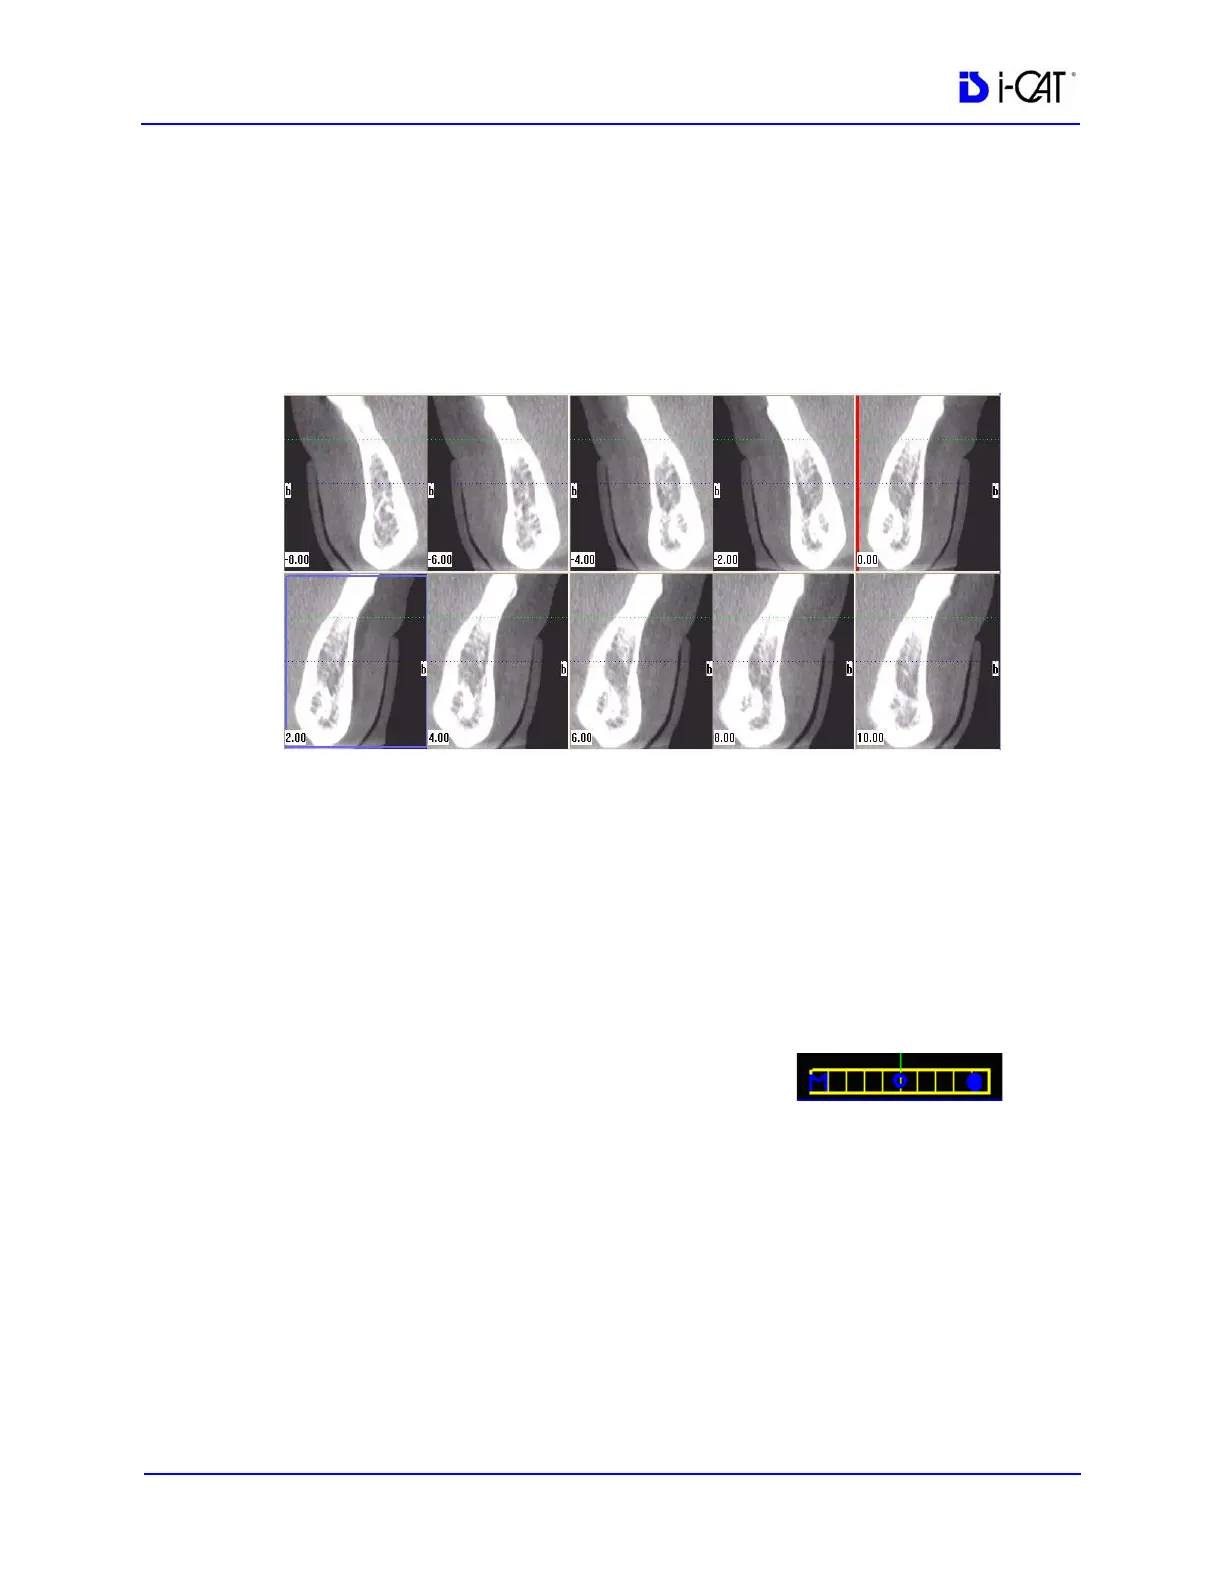

The blue hash mark represents the center line of the axial slices

displayed on the cross section views. (The corresponding center

cross section slice is displayed with a blue frame in the cross section

views.) The orange hash marks represent the other axial slices

displayed on the cross section views. At the top of the axial slice

position view, the positions of the rightmost axial cross section,

center cross section, and leftmost cross section are displayed.

The cross section views are located as indicated by the hash marks

displayed in the axial slice position view. If the 0.00 position is

displayed, it is outlined in red. All slices to the patient’s right side

are displayed as negative numbers. All slices to the patient’s left side

are displayed as positive numbers.